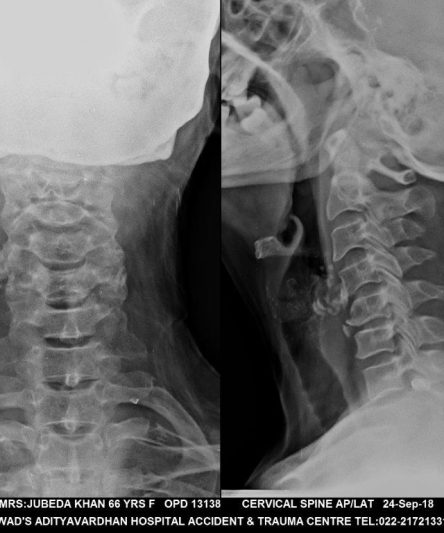

Microskan with Ultra high frequency can take the Lateral Lumbar Spine image of a 90 kg Patient with the correct image receptor